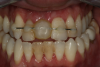

After 4 months of healing and integration of the bone around the implant, the digital workflow was initiated to develop the abutment and treatment plan. Another analog impression was made with an impression post and polyvinyl impression. The laboratory scanned the impression and digitized it to create the emergence profile of the milled titanium abutment and the final restoration (Figure 10 and Figure 11). The patient had a considerably thick soft-tissue profile, allowing a milled titanium abutment. The decision to use a titanium abutment was based on the patient's occlusion and propensity to fracture teeth or restorations. The virtual model was gray because the scanner does not recognize the color of the analog impression. The virtual final abutment and crown were approved and fabrication completed. The final restoration met the patient's esthetic values and his ability to function (Figure 12 and Figure 13).

Fig 10. Titanium abutment proposal.

Figure 10

Fig 11. Final crown proposal.

Figure 11

Fig 12. Six months after cementation.

Figure 12

Fig 13. Radiograph 6 months after cementation.

Figure 13